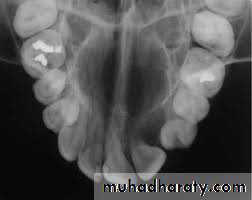

A. Intra oral (periapical, bitewing, occlusal)